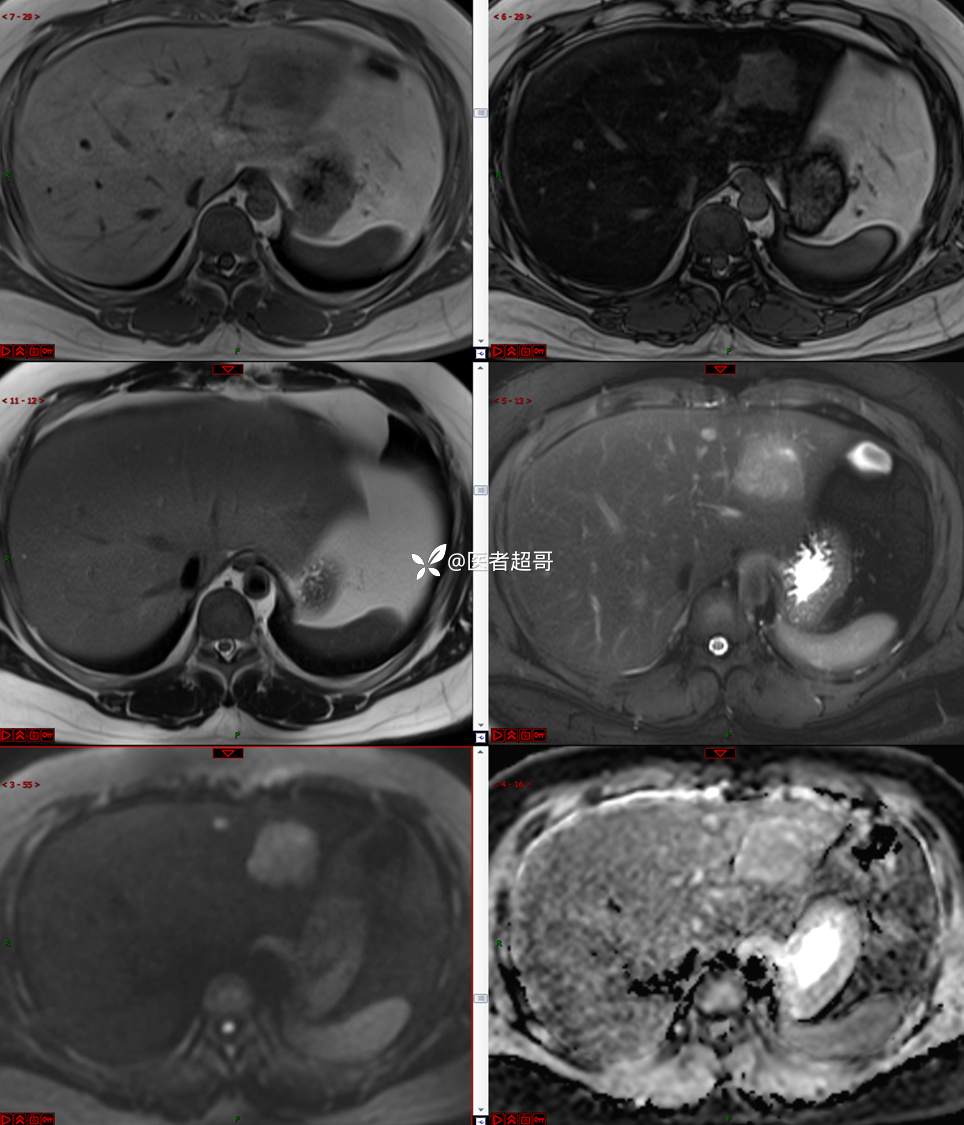

【影诊笔记800】青年男性,肝脏占位,特殊对比剂提示富血供,您能想到啥?有结果!

男,31y

主 诉:发现肝占位性病变5天。

现病史:患者缘于5天前体检时发现肝占位性病变,未予以特殊处置。现患者为求系统诊治就诊于我院,行普美显提示:肝左叶富血供占位,请结合临床及其他检查,肝多发血管瘤,脂肪肝,肝囊肿,请结合临床。门诊以“肝占位性病变”收入我科。病程中,饮食睡眠可,二便可,近期体重未见明显变化。